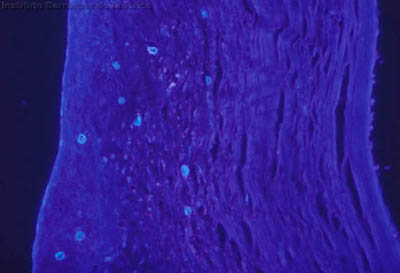

Tinción CW

Blanco de Calcofluor + Azul de Evans

Magnificación 160x

Tejido corneal Procesado

CW